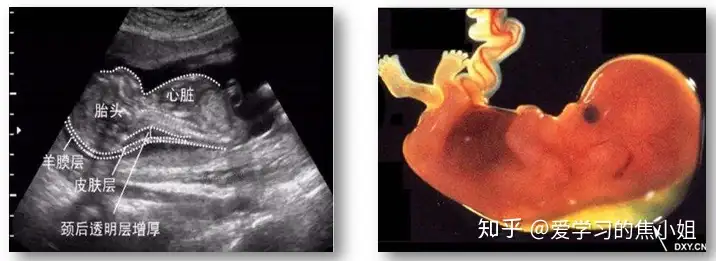

一、胎儿颈部透明层厚度(NT)

颈部透明度厚度( nuchal translucency ,NT):指胎儿颈椎水平冠状切面皮肤至皮下软组织之间的最大厚度,正常胎儿存在此透明区代表胎儿生理性新陈代谢所产生的液体积存。

正常:NT厚度因孕龄不同而不同,随胎儿头臀长而上升;正常在0.25cm以内。

异常标准:孕10周≥1.8mm,孕11周≥1.9mm,孕12周≥2.1mm,孕13周≥2.2mm。目前仍采用NT大于3mm异常标准。NT增厚越明显,发生胎儿结构异常与染色体异常的概率越大。

二、颈后皮肤厚度增加

测量方法:胎儿横切面,显示透明度及丘脑后,探头向后成角清晰显示小脑,在中线水平测量颅骨外侧缘及皮肤外侧缘间的距离。检查时间:16-24周。通常≥6mm视为增厚。14周之后,NT增厚通常会消退,但在部分个案中会演变成颈部水肿或颈部水囊。